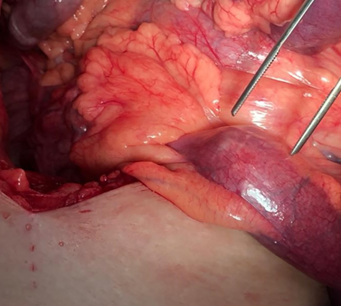

Diaphragmatic hernia before and after reduction of the stomach (Courtesy Dr. V. Penopoulos)